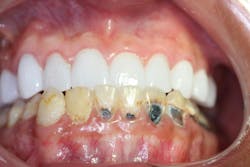

No. 5: Outcome

- Functional and esthetic success

- No complications; improved self-image and quality of life

Restorative and prosthetic rehabilitation in SCD patients must integrate medical management with patient-centered care. Attention to systemic vulnerabilities such as ischemia, infection risk, and stress triggers is crucial. Voco materials used in this case demonstrated excellent adaptability and biocompatibility, contributing to durable outcomes.

The psychosocial benefits of esthetic improvement—particularly in young adults—are considerable. Cosmetic dentistry plays a therapeutic role, improving not only function but also patient confidence and social interaction.